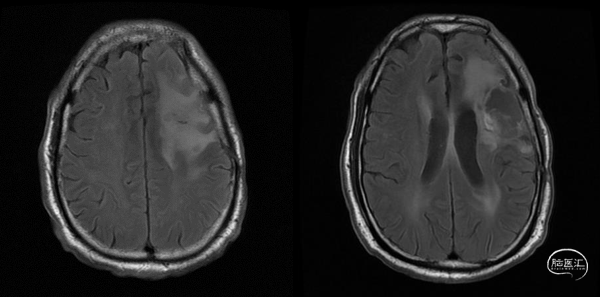

术后48小时MR,可见左额不规则混杂信号影,周围水肿:图示。

术后48小时MR,增强后边缘不规则线样强化,靠近放射冠及侧脑室壁可疑少许残存:图示。

入院前头MRI(2020-3):左侧额岛叶肿块,信号不均匀,其内可见出血和坏死,占位效应明显,周围见水肿。考虑左额岛叶肿瘤(高级别脑胶质瘤可能性大)。于2020年4月行左额岛叶占位性病变切除术。术中见肿瘤组织位于左侧额中回及额下回后部,大小约4m×5cm×5cm,呈烂鱼肉样,色灰红,质软,部分坏死,血运中等,边界不清,侵犯左侧岛叶向下挤压颞叶。显微镜下沿肿瘤周边胶质增生带完整切除肿瘤。术后48小时内复查头MRI平扫、加强,影像显示术腔边缘不规则线样强化,靠近放射冠及侧脑室壁强化明显,可疑少许残存。